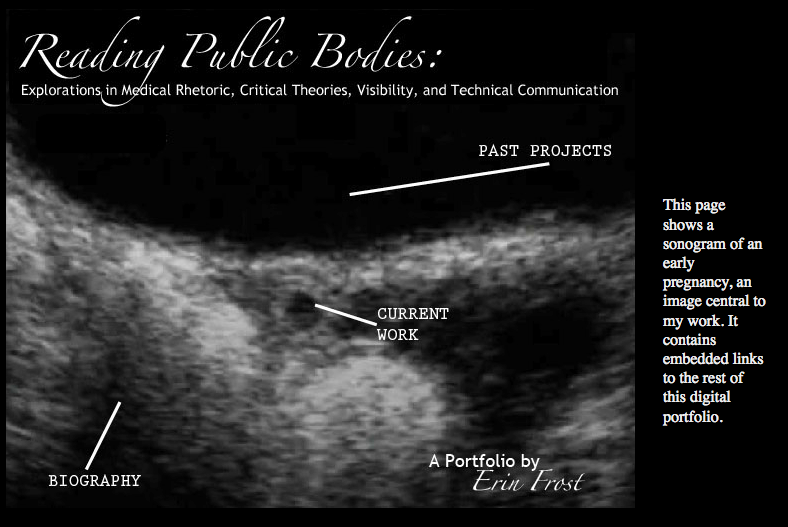

I’m more than a little embarrassed that it’s been so long since I’ve posted anything substantial. I got caught up in my last semester of master’s studies. On the bright side, that means I have new and interesting visual rhetoric news to report. I finished a portfolio rather than a thesis to earn my master’s, which means I was able to utilize visibility in a way that would not have been possible otherwise. I’m so impressed with ISU for allowing this option. I’m continuing to research in the areas it highlights and so am always interested in constructive feedback.